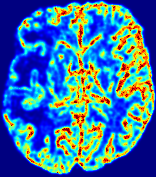

LesionRefer to captionRefer to captionRefer to captionRefer to captionRefer to captionRefer to caption𝐕rgbsubscript𝐕𝑟𝑔𝑏{\bf{V}}_{rgb}Refer to captionRefer to captionRefer to captionRefer to captionRefer to captionRefer to caption𝐕2subscriptnorm𝐕2{\|\bf{V}}\|_{2}Refer to captionRefer to captionRefer to captionRefer to captionRefer to captionRefer to captionRefer to caption3.53.53.52.82.82.82.12.12.11.41.41.40.70.70.70.00.00.0(mm/s)𝑚𝑚𝑠(mm/s)D𝐷DRefer to captionRefer to captionRefer to captionRefer to captionRefer to captionRefer to captionRefer to caption0.0200.0200.0200.0160.0160.0160.0120.0120.0120.0080.0080.0080.0040.0040.0040.0000.0000.000(mm2/s)𝑚superscript𝑚2𝑠(mm^{2}/s)Slice #1Slice #2Slice #3Slice #4Slice #5Slice #6

Figure 3: PIANO feature maps for one stroke patient, where the lesion is located in the left hemisphere. Top row: segmented stroke lesion region (white) on different slices, obtained from ISLES 2017. The corresponding slices for the PIANO feature maps are shown in the following rows.

For a better insight into an estimated velocity field 𝐕𝐕{\bf{V}} and diffusion field 𝐃𝐃{\bf{D}}, we compute the following maps: (1) 𝐕rgbsubscript𝐕𝑟𝑔𝑏{\bf{V}}_{rgb}: Color-coded orientation map of 𝐕=(Vx,Vy,Vz)T𝐕superscriptsuperscript𝑉𝑥superscript𝑉𝑦superscript𝑉𝑧𝑇{\bf{V}}=(V^{x},V^{y},V^{z})^{T}, obtained by normalizing 𝐕𝐕{\bf{V}} to unit length and mapping its 3 components to red, green, blue respectively; (2) 𝐕2subscriptnorm𝐕2\|{\bf{V}}\|_{2}: 222 norm of 𝐕𝐕{\bf{V}}; (3) D𝐷D: scalar field in Eq. 5.

Fig. 3 and Fig. 4 show the PIANO feature maps estimated from two ISLES 2017 patients: all are highly consistent with the lesion in both cases. Details of the blood flow trajectories are revealed in 𝐕rgbsubscript𝐕𝑟𝑔𝑏{\bf{V}}_{rgb} by the ridged patterns and the sharp changes of colors in the unaffected (right) hemisphere, while the flat patterns appearing within the lesion provide little directional information about the velocity and indicate low velocity magnitudes. Velocity magnitudes are more directly visualized via 𝐕2subscriptnorm𝐕2\|{\bf{V}}\|_{2}, from which one can easily locate the lesion where 𝐕2subscriptnorm𝐕2\|{\bf{V}}\|_{2} is low. D𝐷D also indicates lower diffusion values in the lesion, though with less contrast potentially due to the fact that it captures the accumulated effect of CA diffusion at the voxel-level.